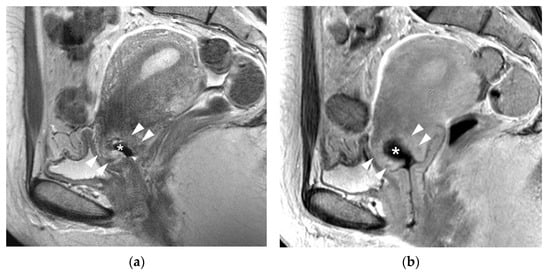

3.1. T2WI Findings

5. Post-Trachelectomy MRI